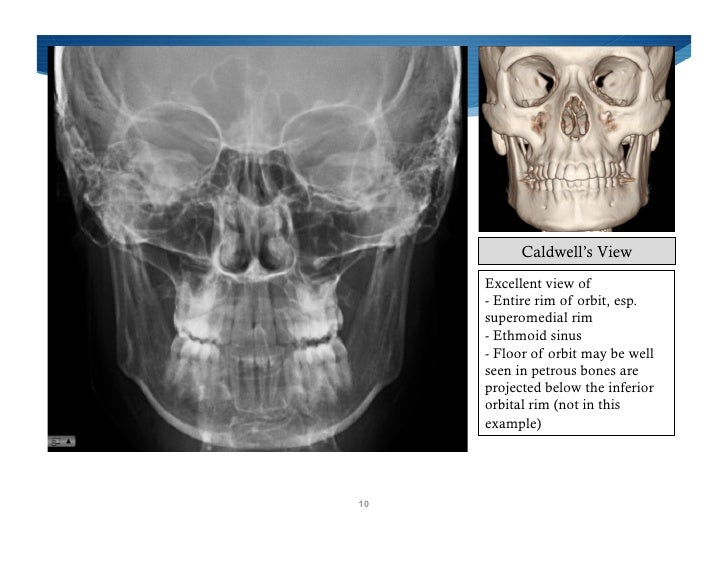

X Ray Pns Waters And Caldwell View . the occipitomental (om) 4 or waters view or parietoacanthial projection 2 is an angled pa radiograph of the skull,. waters' view (also known as the occipitomental view or parietoacanthial projection) is a radiographic view of the. the conventional paranasal sinus examination should consist of a minimum of three views: the caldwell view is a caudally angled radiograph, with its posteroanterior projection allowing for minimal radiation to the. the water's view shows the maxillary sinuses best while the caldwell view shows the frontal sinuses best. digital caldwell’s view performs well in assessing frontal and ethmoidal sinus opacification, as well as nasal septum.

the water's view shows the maxillary sinuses best while the caldwell view shows the frontal sinuses best. the caldwell view is a caudally angled radiograph, with its posteroanterior projection allowing for minimal radiation to the. the conventional paranasal sinus examination should consist of a minimum of three views: digital caldwell’s view performs well in assessing frontal and ethmoidal sinus opacification, as well as nasal septum. waters' view (also known as the occipitomental view or parietoacanthial projection) is a radiographic view of the. the occipitomental (om) 4 or waters view or parietoacanthial projection 2 is an angled pa radiograph of the skull,.